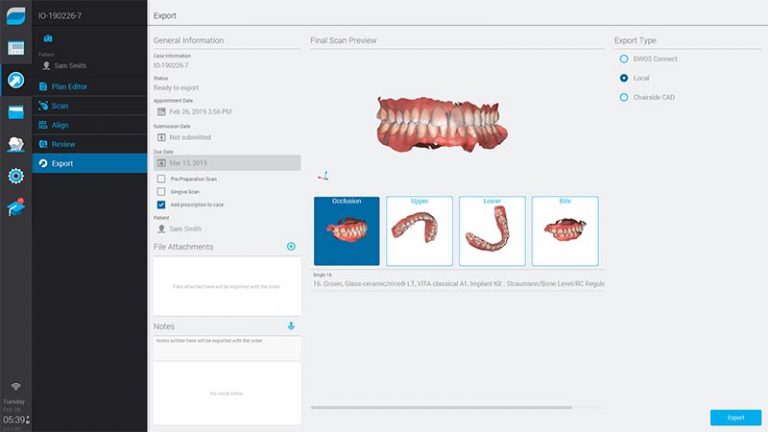

Nosso Scanner elimina algumas etapas clínicas e ainda evita possíveis erros de distorções, garantindo mais precisão para o seu processo.

Com nossa tecnologia a confecção de aparelhos, lentes de contato e até mesmo próteses é extremamente simples, eliminando completamente a necessidade da moldagem.

Em apenas alguns minutos todas as informações necessárias são coletadas, sem nenhum processo desconfortável.

Resultados em tempo real são prontamente enviados e analisados pelos profissionais responsáveis, reduzindo drasticamente o tempo necessário para as próximas etapas.